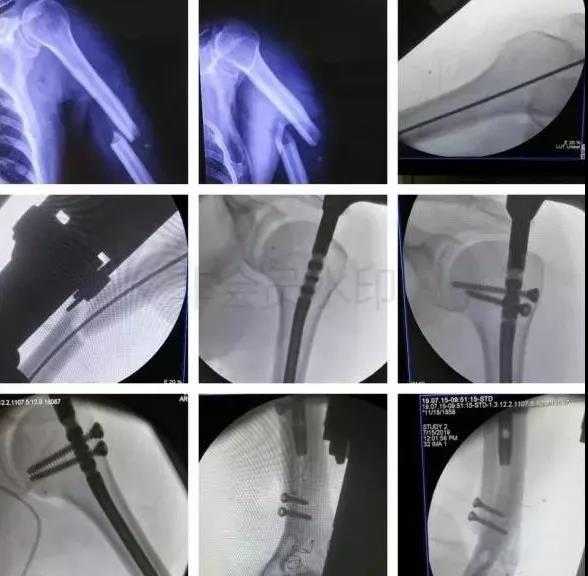

1)肱骨近端骨折

脱位伤及腋神经、血管等,或者由于肱二头肌长头腱卡压无法复位,立即手术。

- 内固定方式很多,如DHS,pfna等。